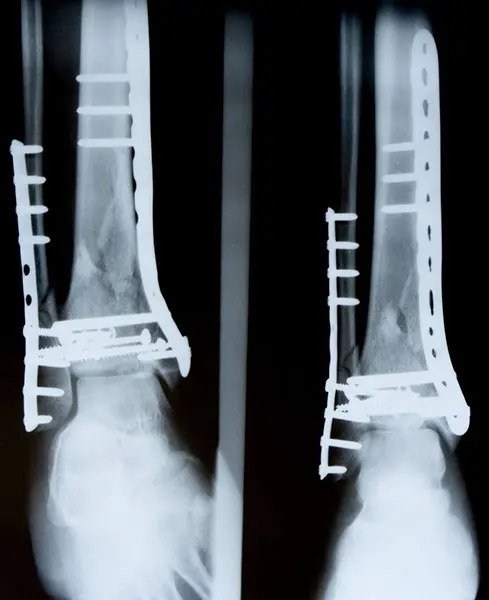

ASTM F384 is a testing standard that defines the geometric and performance characteristics of metallic angled devices. This standard covers both static and fatigue test methods to determine the mechanical properties of metallic angled orthopedic fracture fixation devices and covers two test methods:

- Test Method for Single Cycle Compression Bend Testing of Metallic Angled Orthopedic Fracture Fixation Devices: This method measures the bending stiffness and the bending strength and determines the intrinsic, structural properties of metallic angled fracture fixation devices.

- Test Method for Determining the Bending Fatigue Properties of Metallic Angled Orthopedic Fracture Fixation Devices: This method may be used to determine the fatigue life of angled devices at a specific or over a range of maximum bending levels, or to estimate the fatigue strength for a specified number of cycles.